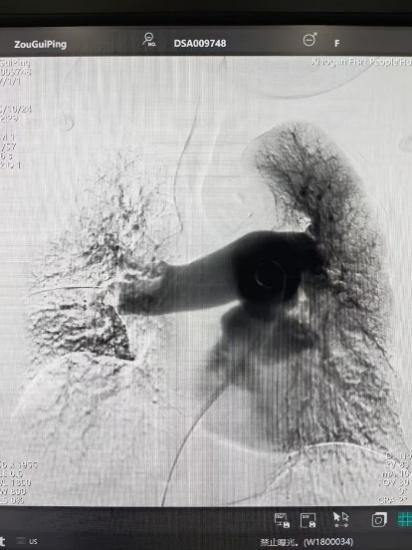

術(shù)后

手術(shù)在局部麻醉下進(jìn)行,團(tuán)隊(duì)通過(guò)股靜脈穿刺,將專(zhuān)用抽栓導(dǎo)管精準(zhǔn)送達(dá)肺動(dòng)脈栓塞部位,利用負(fù)壓抽吸技術(shù)成功清除大量血栓;隨后,在血栓局部精準(zhǔn)灌注溶栓藥物,進(jìn)一步溶解殘余血栓,恢復(fù)肺部血流灌注;同時(shí),為防止下肢深靜脈血栓再次脫落引發(fā)肺栓塞,團(tuán)隊(duì)為患者置入下腔靜脈濾器,整個(gè)手術(shù)歷時(shí)約1小時(shí)。術(shù)后,鄒婆婆呼吸困難癥狀即刻得到緩解,血氧飽和度顯著提升,右心負(fù)荷明顯減輕,目前身體狀況正在逐步恢復(fù)中。